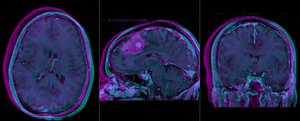

Registration Results

RegLib C01 unregistered.png baseline and follow-up before registration (click to enlarge)

RegLib C01 rigid.png after rigid alignment. Note the residual shape differences (click to enlarge)

RegLib C01 affine.png after affine registration (click to enlarge)

• The affine registration seeks to address residual distortions that are typical for longitudinal MRI. However to prevent the tumor (and putative tumor change) from affecting the registration, we mask out the tumor so that it does not contribute to the registration. The assumption is thus that aside from the tumor we expect the two serial scans to be matching exactly, i.e. any differences in size or shape is considered an artifact we wish to remove by registration.